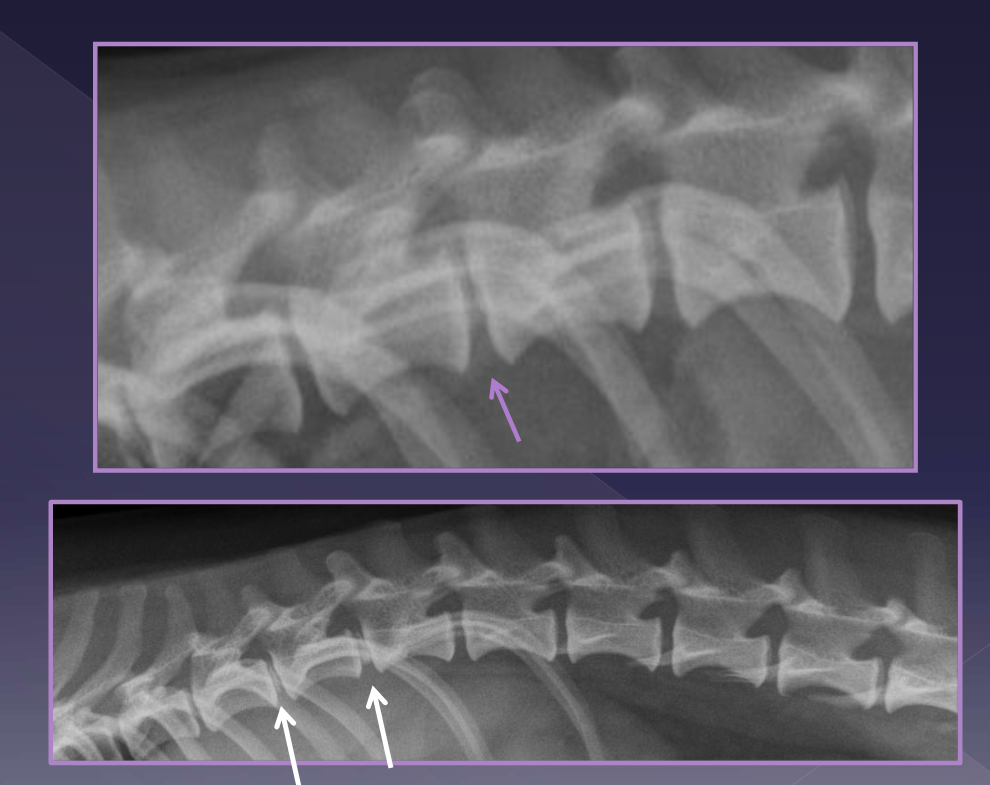

radiographs

spondylosis

narrowed disc

endplate sclerosis

transitional vertebrae

CT

MRI - way to go but CT will work